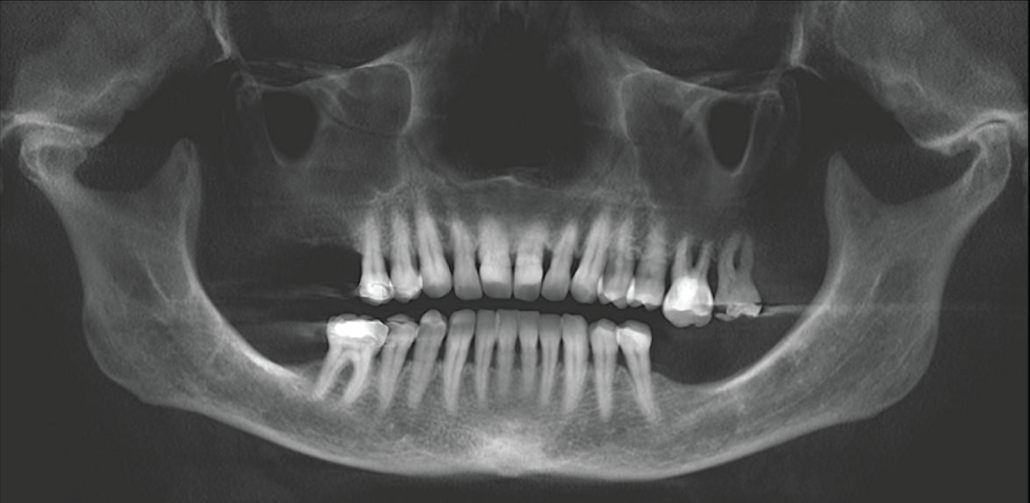

CBCT reconstructed panoramic image.